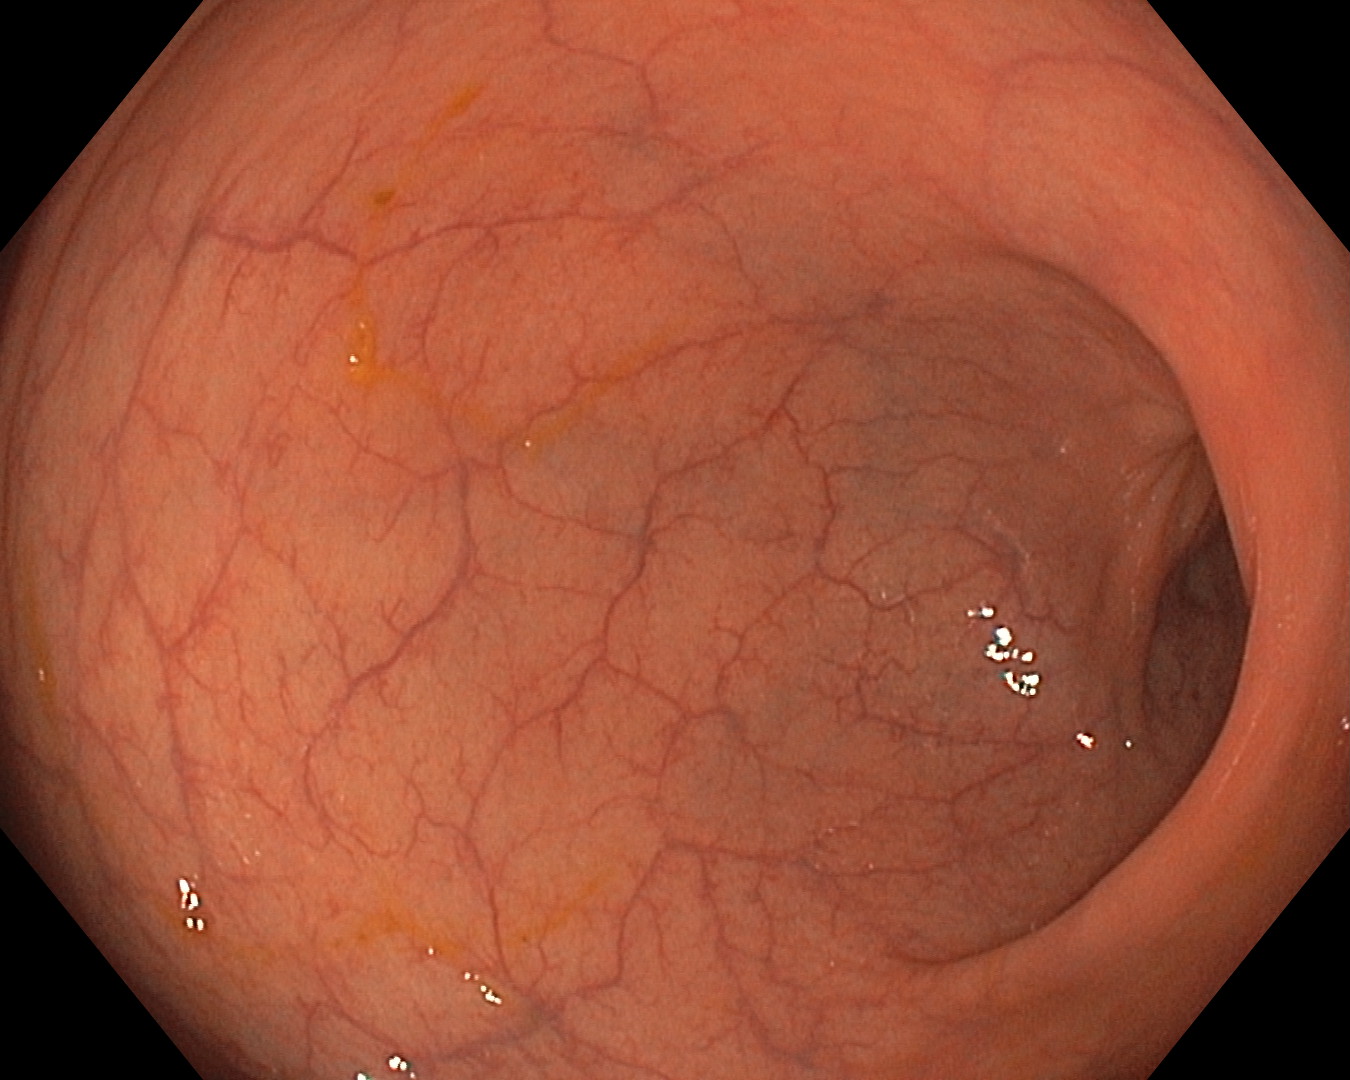

Loša priprema za kolonoskopiju: crijevni sadržaj onemogućava pregled sluznice debelog crijeva | Dobra priprema za kolonoskopiju: jasno se vidi sluznica debelog crijeva |

Ako crijevo nije čisto, otvara se mogućnost previda značajne patologije u lumenu (unutrašnjosti crijeva), stoga u Centru za ekspertnu medicinu posebnu i koristimo individualizirane protokole za pripremu bolesnika za kolonoskopiju

Pored toga koristimo suvremene dijagnostičke aparate s mogućnošću prikaza u uskopojasnom spektru („narrow band imaging“), kao i digitalnim povećanjem, čime nam je omogućena minuciozna analiza sluznice debelog crijeva i time dodatno poboljšavamo dijagnostičku preciznost pretrage.